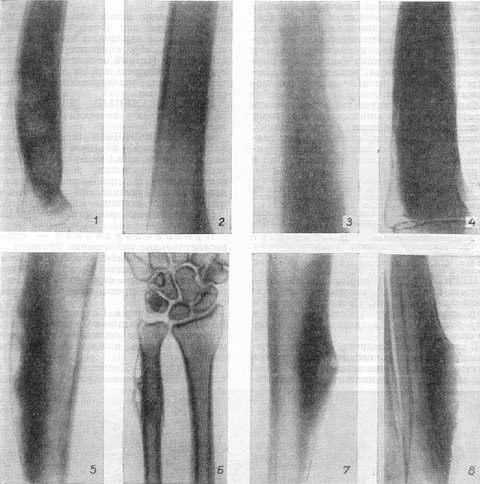

Рис. 3. Рентгенодіагностика періоститу: 1 - лінійні чіткі тіні неассимилированного періостального остеофита при рецидиві хронічного остеомієліту плечової кістки; 2 - лінійна неінтенсивна, нечітка тінь свіжого неассимилированного періостального остеофита поблизу задньої поверхні діафіза стегна при гострому остеомієліті тритижневої давності; 3-тінь частково накопиченого періостального остеофита з торочкуватими обрисами при «пухлиноподібний» остеомієліті стегна; 4 - ніжні голчасті тіні кісткоутворення уздовж судин окістя; 5 - ассимилированный щільний періостальний остеофіт на передній поверхні великогомілкової кістки з узурами при гуммозном остеопериостите; 6 - ассимилированный періостальний остеофіт з мереживним малюнком внаслідок дірчастих просвітлінь (гуми) на диафизе ліктьової кістки при гуммозном і дифузному остеопериостите; 7 - інтенсивна, слившаяся з кірковим шаром великогомілкової кістки тінь накопиченого періостального остеофита при хронічному кортикальному абсцесі; порожнину з секвестром в товщі остеофита; 8 - розташована асиметрично тінь накопиченого періостального остеофита великогомілкової кістки при хронічній трофічної виразки гомілки.